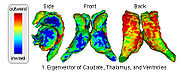

DTI-based SegmentationUnlike conventional MRI, DTI provides adequate contrast to segment the thalamic nuclei, which are gray matter structures. More... |

Population Analysis of Anatomical VariabilityOur goal is to develop mathematical approaches to modeling anatomical variability within and across populations using tools like local shape descriptors of specific regions of interest and global constellation descriptors of multiple ROI's. More... |